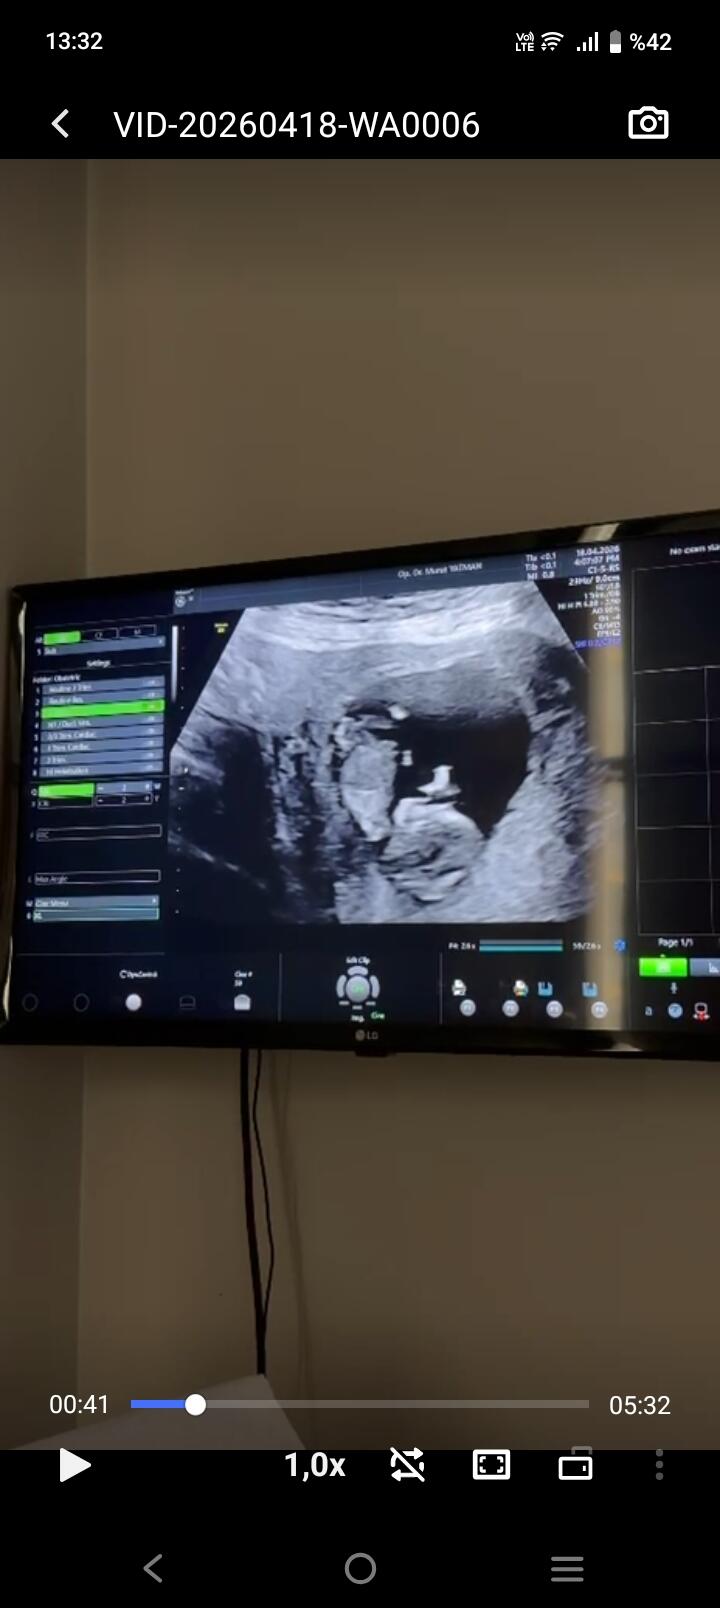

Neye bakarak erkek hissi verdi . Bende ayırt etmek istiyorum çünkü bakınca bana hem kız hissi veriyor hem erkek ![]()

Canım çok net değil ama başka var mı yakin ve net tahmin edecek olursak erkek bebek gibi

Anladım baş aşağı durduğunu orda çıkıntı var o yüzden erkek gibi geldi kordon değil ise